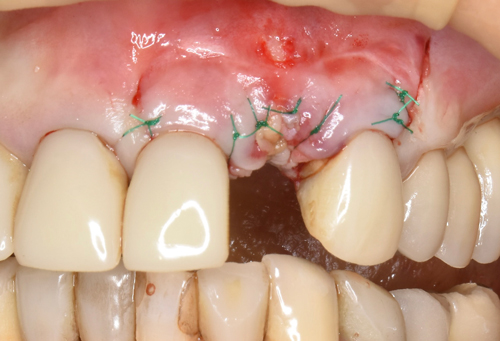

初診時、歯茎から出来物の腫れを認めます。これが1年以上続いているとのこと。

増設した人工の骨をより定着させるために、血液から作ったコラーゲン膜を何層にも敷き詰めていきます(無料)。あとは仮歯を施して、骨が固定するのを6ヶ月間待ちます。